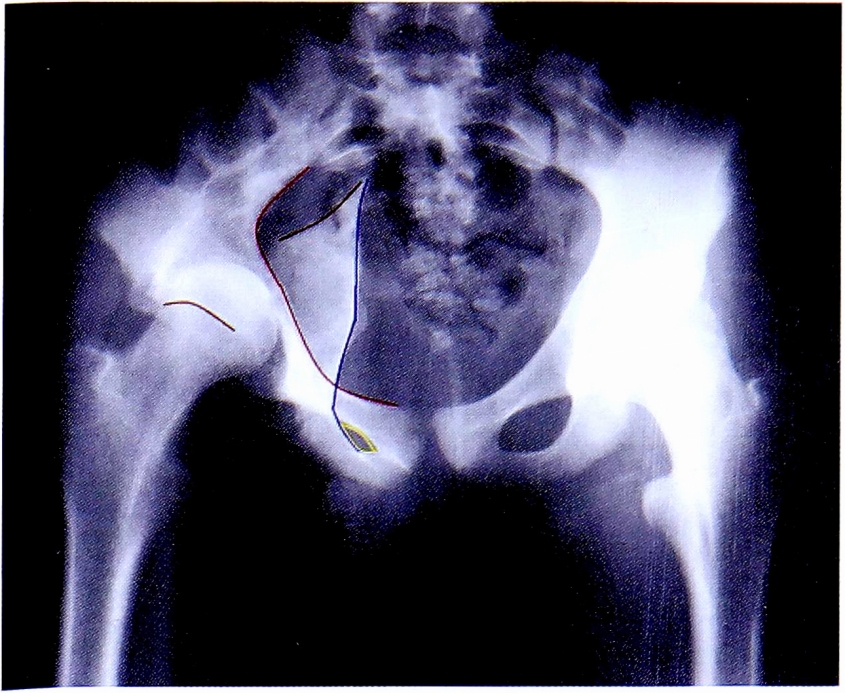

Определение типа перелома выполняют последовательным ответом на вопрос: имеется повреждение определенной линии или нет. Анализ контуров каждой референтной линии позволяет исключить определенные типы переломов. Основными линиями, позволяющими последовательно определить тип перелома, являются: подвздошно-гребешковая линия, подвздошно-седалищная линия, контуры запирательного отверстия, линия задней стенки, крыло подвздошной кости. Каждая из референтных линий на рентгенограммах отмечена определенным цветом (рис. 18).

Рис. 18. Цвета референтных линий на рентгенограммах.

Fig. 18. Reference lines colours on X-rays.